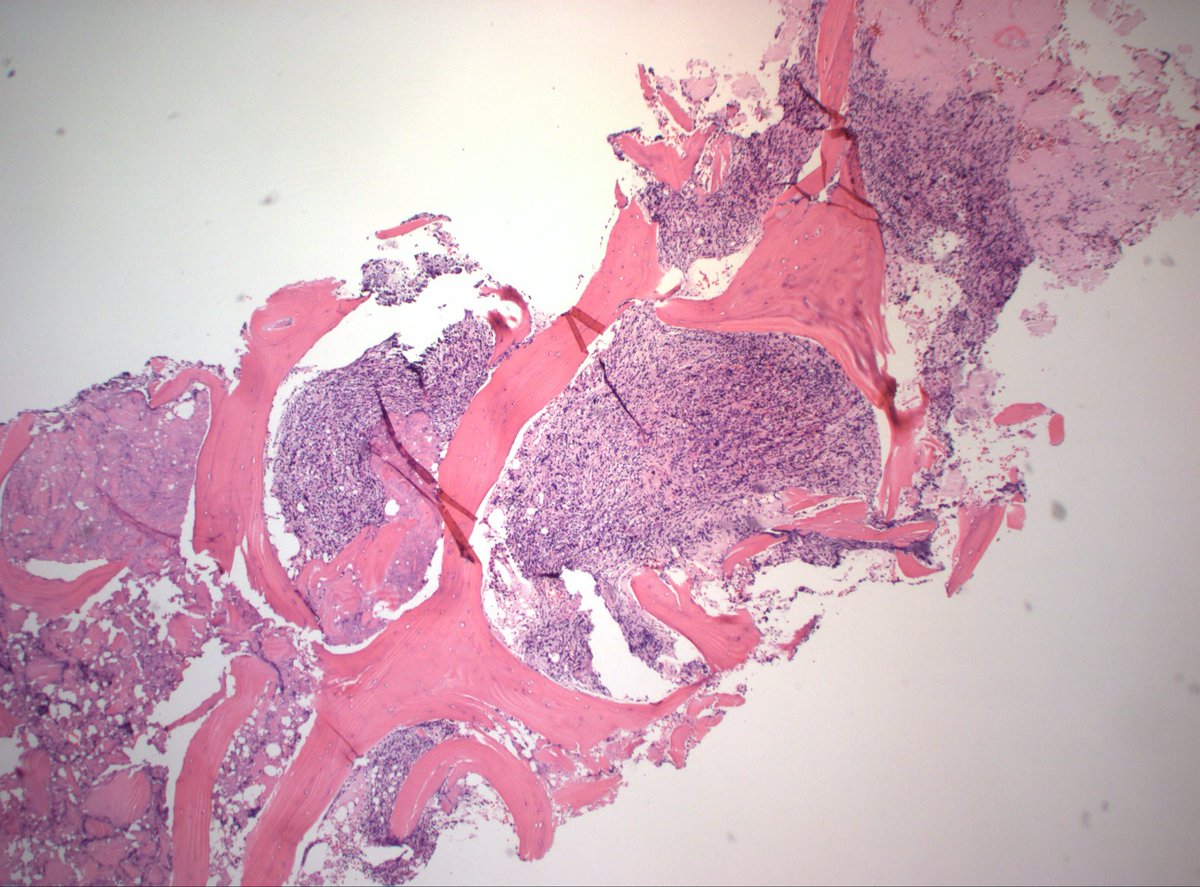

A 35 Yr | 👨 "Cyst Chronicles: Secrets of the premolar prison" ● Right Mandible 🎯 Shoot your 2 most favored DDx's @Pathologists #PathTwitter #pathX #pathresidents #HeadandNeckPath